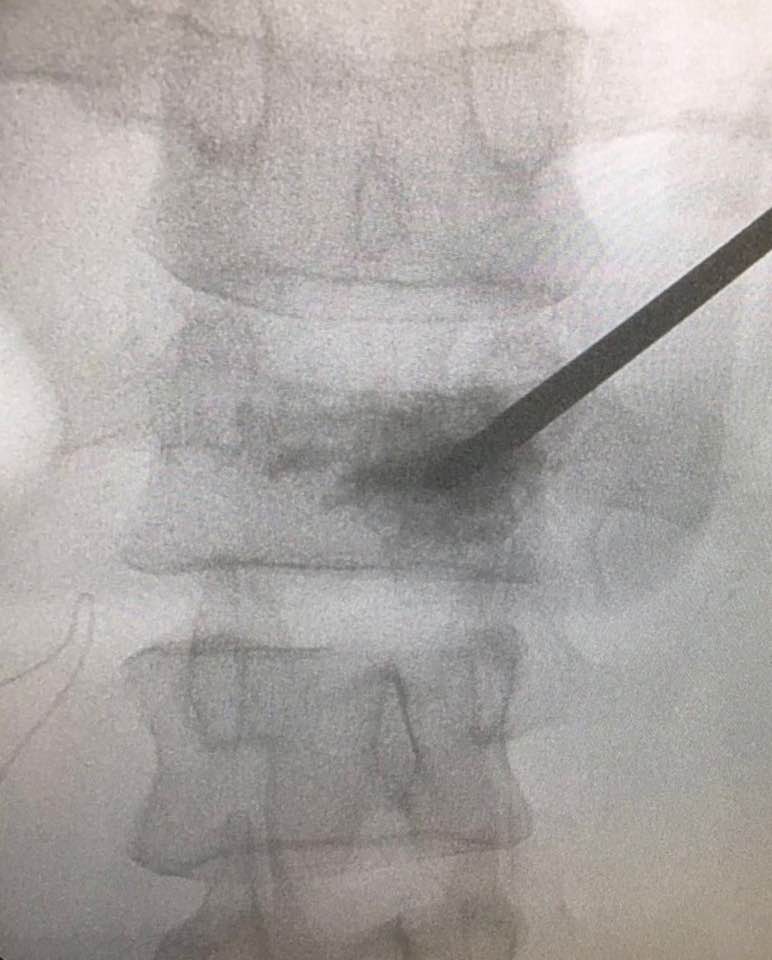

嚴重的工業意外受傷,T12胸脊椎不穩定的3段(前、中、後柱列)壓迫性脊柱椎體骨折

1. 即使您的胸部及胸脊椎柱被8英尺高和200磅重的巨大雪櫃嚴重壓碎, 您仍然生存, 您的中樞脊髓神經但沒有受到傷害.

2. 即使公立醫院忽畧了你不穩定的前、中、後3柱列的T12胸脊椎骨折,並在3天後容許你出院送回家, 你到私家醫院再進行第二次詳細檢查!

3. 幸運的是,入院前及兩天來你未有因為不穩定的脊柱椎體骨折碎片的移位而導致你脊髓中樞神經到不可逆轉和永久性的損傷致雙腿癱瘓及大小便失禁. 今天所有穩定你碎裂脊椎的手術都做完了.